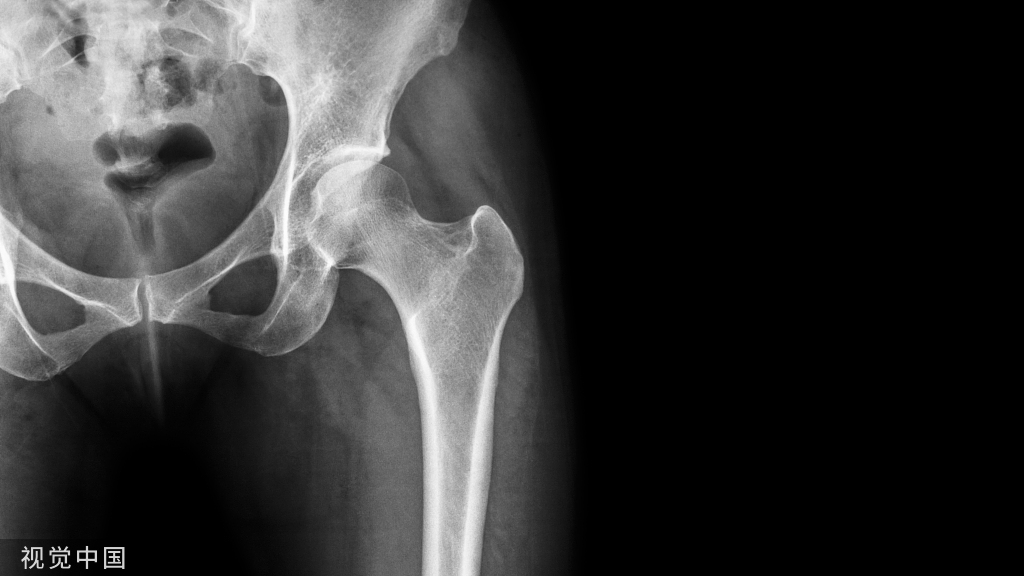

文献来源:

Verlinsky L, Ulmer C, Rose A,Improved Outcomes in Operative Management of Concomitant Distal Radius and Scaphoid Fractures.Hand (N Y) 2023 Apr 12.